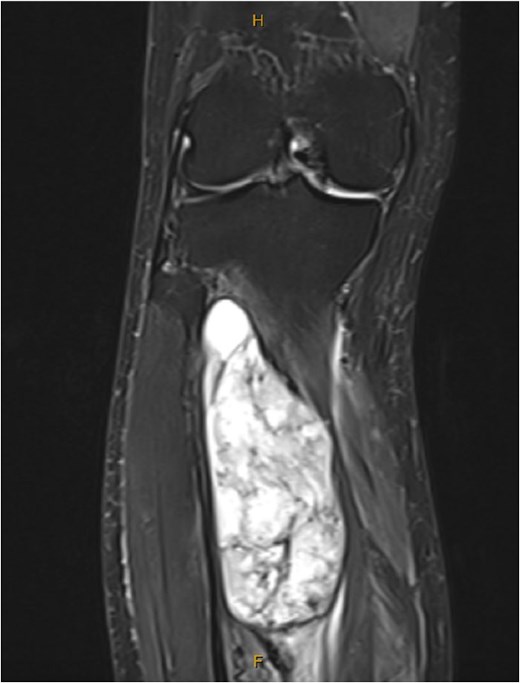

One year after the second discontinuation of imatinib, at age 82, the patient presented with progressive right leg swelling and pain. Magnetic resonance imaging (MRI) identified a 10 cm mass within the tibialis posterior muscle (Fig. 3). Biopsy confirmed metastatic GIST, positive for KIT, DOG1, and CD34. Imatinib therapy was restarted and adjuvant radiotherapy was under consideration at the time of reporting.

MRI showed a large tibialis posterior intramuscular lesion with proximal tibial involvement.